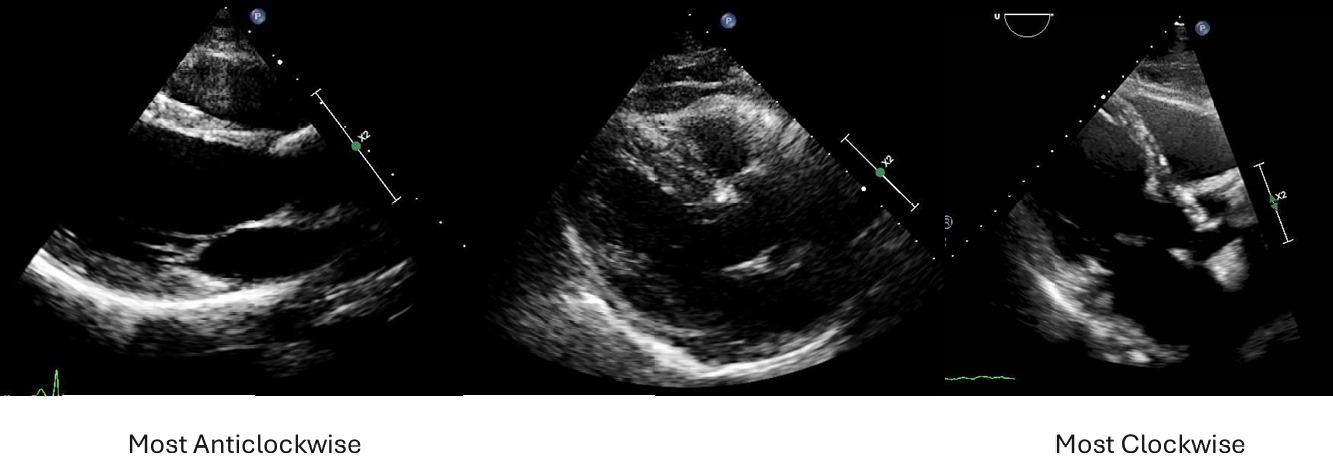

Excessive clockwise rotation is a common issue in the Parasternal Long Axis (PLAX) echocardiographic view.

We are training an AI to automatically understand and assess PLAX image rotation by arranging images in order — from the most anticlockwise (rare) through the middle zone of acceptability, to the most clockwise.

Visual Example

PLAX Orientation Example